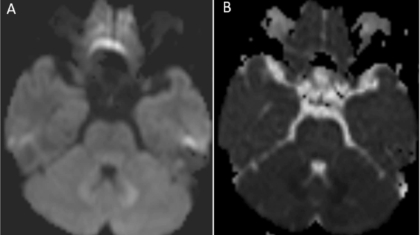

53 year old female presented with complains of gait imbalance and ataxia.

She has chronic kidney disease and was recently started on anti tubercular therapy(ATT) for pulmonary tuberculosis